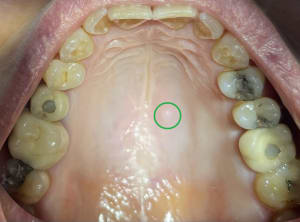

mise en charge immédiate 2.jpg